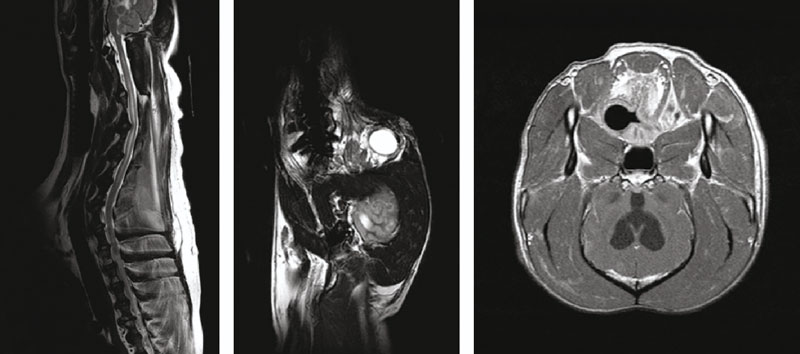

МРТ-АМИКО — медицинское оборудование, разработанное на основе технологии постоянного магнита. Оно отличается экономичностью, компактностью, низкими затратами на обслуживание и высокой диагностической точностью, что особенно важно для ветеринарной медицины.

Технологии активного экранирования контура, а также шиммирования высокого порядка и быстропоточная конструкция эффективности полюсов обеспечивают эффективность исследования и получение снимков высокого качества.